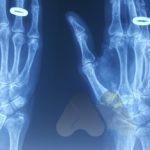

Carpal tunnel syndrome affects the median nerve that travels through a space that connects the forearm and hand at the front of the wrist. Pressure on the nerve, from many possible causes, can lead to a slowing of the electrical signals that supply sensation to the thumb, index and middle finger. It can lead to tingling and numbness in these fingers or the whole hand and can often be worse at night time.